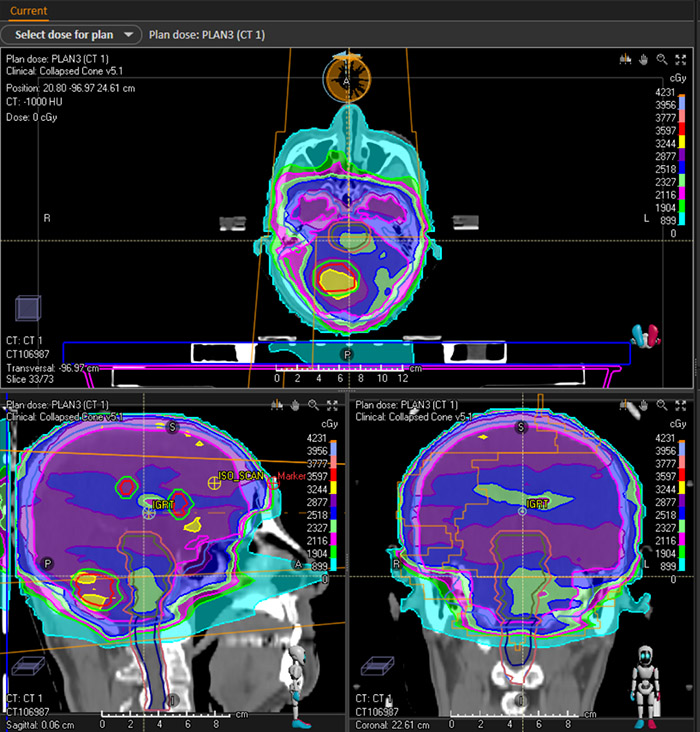

以下是一例肺癌多发脑转移病例的伽玛刀+直线加速器双头计划。通过DVH图以及剂量分布可以发现,比传统的直线加速器治疗,患者靶区的剂量得以提高,危机器官受量相对减少,达到了更佳的临床治疗效果。

剂量分布图

伽玛刀剂量分布图

直线加速器剂量分布图